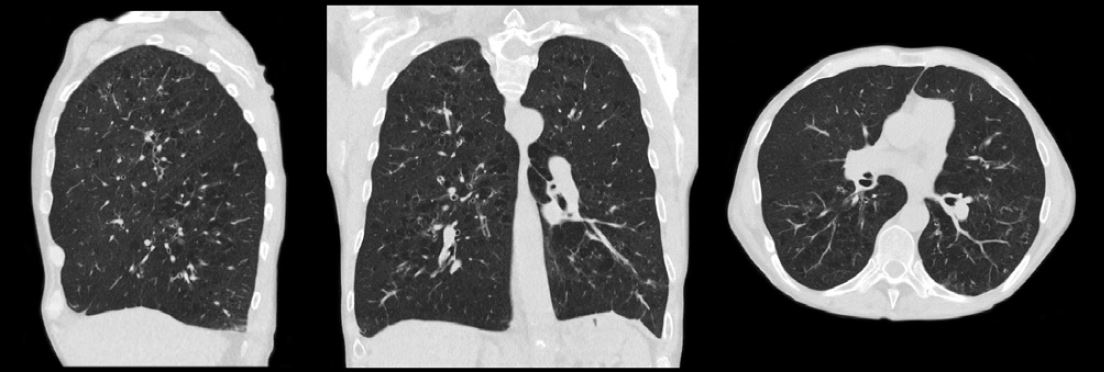

Сканування грудної клітки з SilverBeam пацієнту з емфіземою легень (0,2 мЗв).

Доктор Булл і його команда також використовують фільтр SilverBeam для отримання високоякісних зображень при дуже низькій дозі. «Ми не просто прагнемо досягнути низької дози – ми прагнемо отримати високу якість зображення при низькій дозі. Ми можемо це зробити з

SilverBeam», — зазначив він. «Ми використовуємо його не лише для

скринінгу раку легенів, ми використовуємо його для стандартного зображення грудної клітки. Ми також використовуємо його для візуалізації кісток, тому що ми отримуємо набагато менше артефактів і доза набагато нижча. Якщо це хребет чи пазухи, або якщо ми шукаємо перелом стегна, ми використаємо SilverBeam».

SilverBeam

Фільтр для КТ-систем Aquilion, який містить срібло для вибіркової оптимізації енергії

променя. Він видаляє фотони низької енергії зі спектру променя, які не впливають на якість зображення, але збільшують дозу та

розсіювання. У поєднанні з технологією Advanced intelligent Clear IQ Engine (AiCE) Canon Medical цей енергетичний фільтр, що формує промінь, може використовувати потужність

штучного інтелекту для забезпечення високої

якості зображення та низького рівня шуму для спеціальних програм.